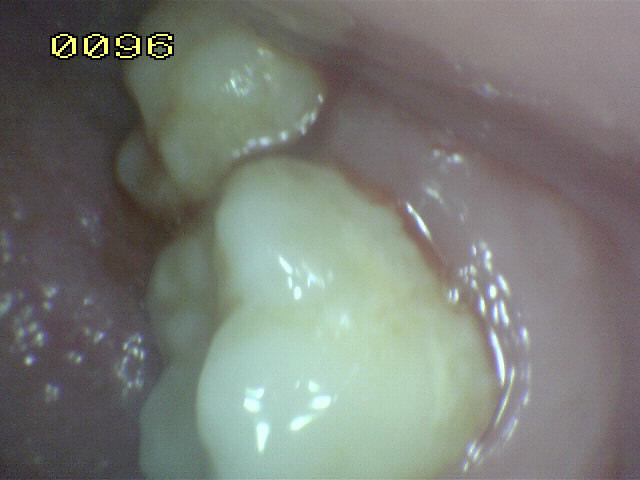

Encía inflamada |

Encía levemente inflamada con un

componente fibroso. Observe el borde gingival con aspecto

liso, turgente y brillante de color rojo |